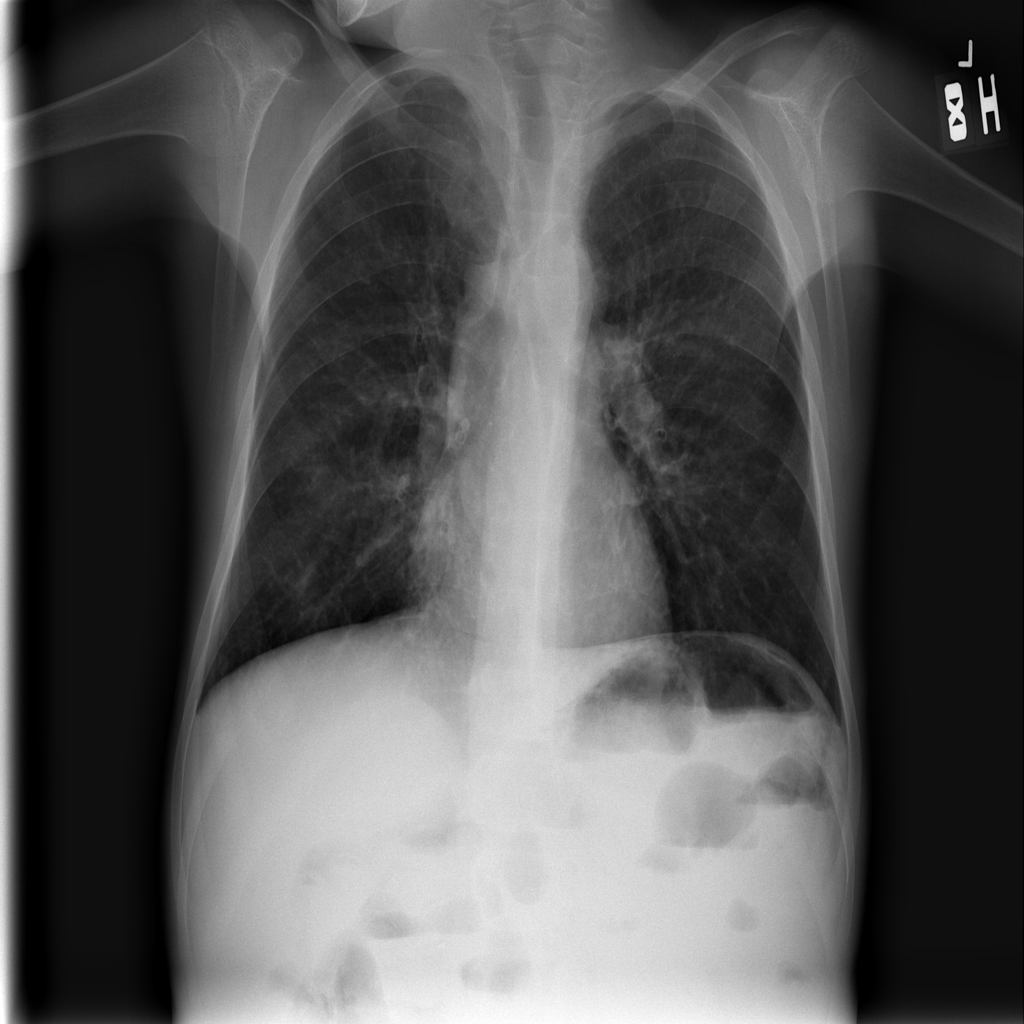

Consolidation

Consolidation refers to air-space filling that makes part of the lung appear denser on imaging.

Showing up to 90 reference images for Consolidation.

PAT-B733 · IMG-000Consolidation

PAT-B733 · IMG-000

PA